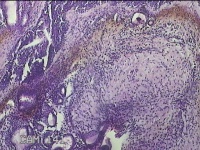

右侧鼻腔新生物

性别

女

年龄

31岁

临床诊断

1.鼻息肉 2.变应性鼻炎

一般病史

反复鼻塞、流涕嗅觉减退1年。

标本名称

大体所见

灰白暗红色不规则碎组织1.5x0.7x0.3cm一块,表面糜烂,内有少许骨质。